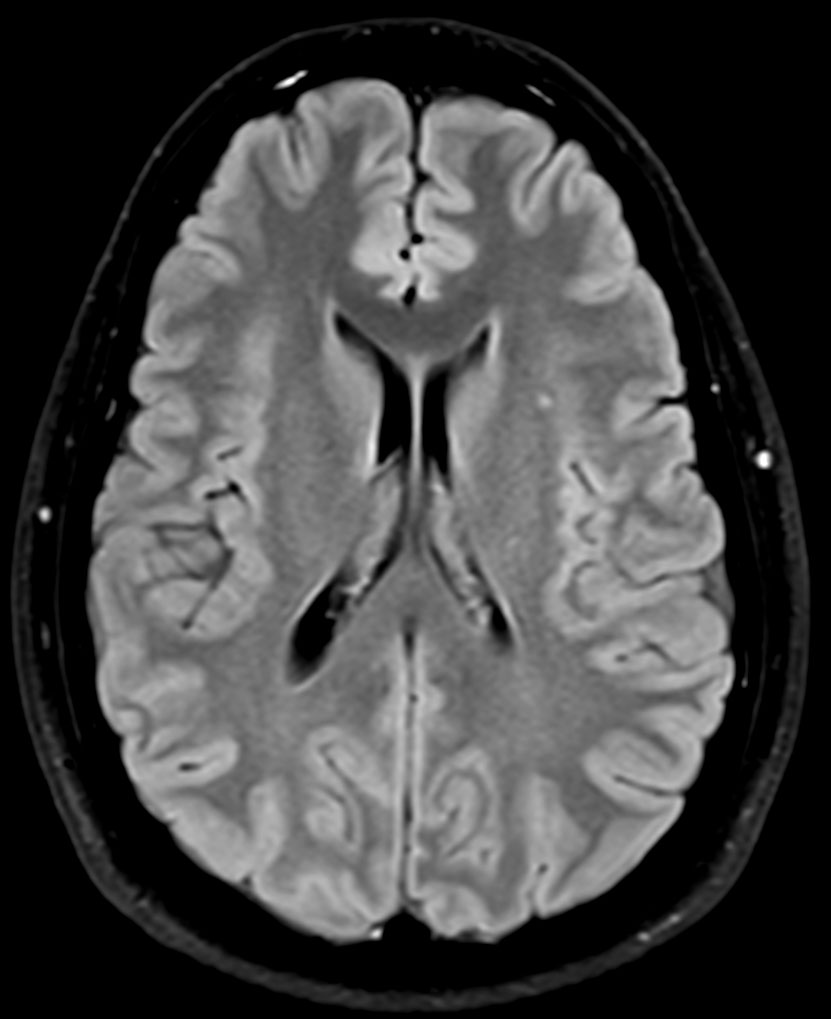

Brain imaging using ComforTone